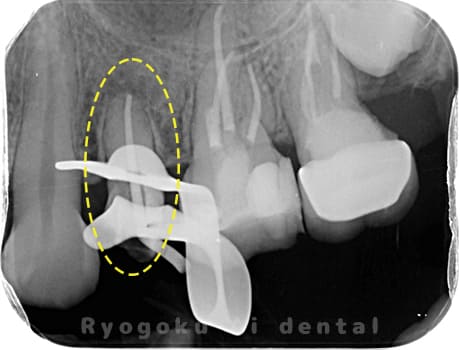

根管内の異物

- 原因

- 根管内異物(ファイル破折)による慢性根尖性歯周炎

- 治療期間

- 3ヶ月

- 治療内容

- マイクロスコープを使用した根管内異物除去並びにマイクロエンド

- 治療費用

- 121,000円(ファイル除去費用も込み)

他院で細い器具(ファイル)が根管内に破折した状態で、咬合痛を主訴に来院された患者様です。ファイルをマイクロスコープ下で除去し、根管治療を行ないました。